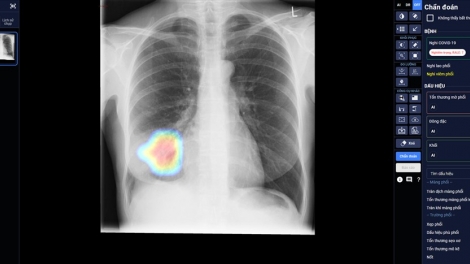

베트남, 인공지능 활용 코로나19 치료 선별 및 진단 도구 첫 개발 성공적

(VOVWORLD) - 빈그룹 산하 빈브레인 AI 활용 상품 코로나19 전용 닥터에이드(DrAid)가 보건부 과학위원회로부터 신속 상용화 건의를 받게 되었다. 닥터에이드는 코로나19 치료 선별 및 진단을 지원하는 효과적인 도구로 예방과 방역에 적극 기여할 것으로 여겨지고 있다.